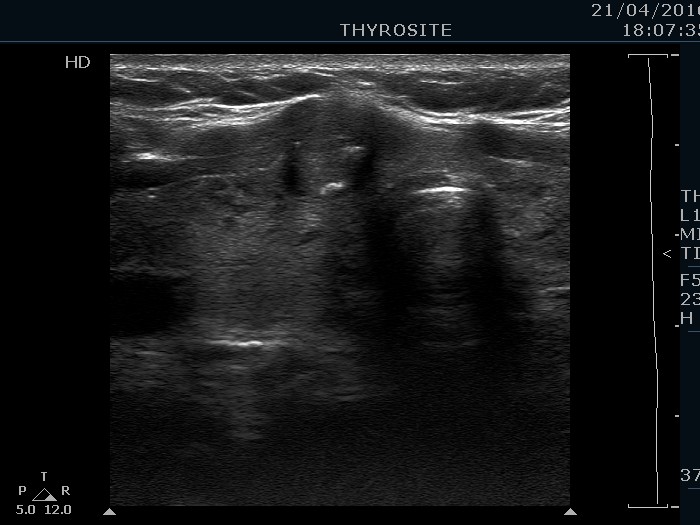

Ultrasonography. The thyroid was echonormal and contained hypoechogenic areas. The echogenicity index was around 20%. There was a moderately hypoechogenic lesion presenting microcalcifications in the ventral part of the right lobe.